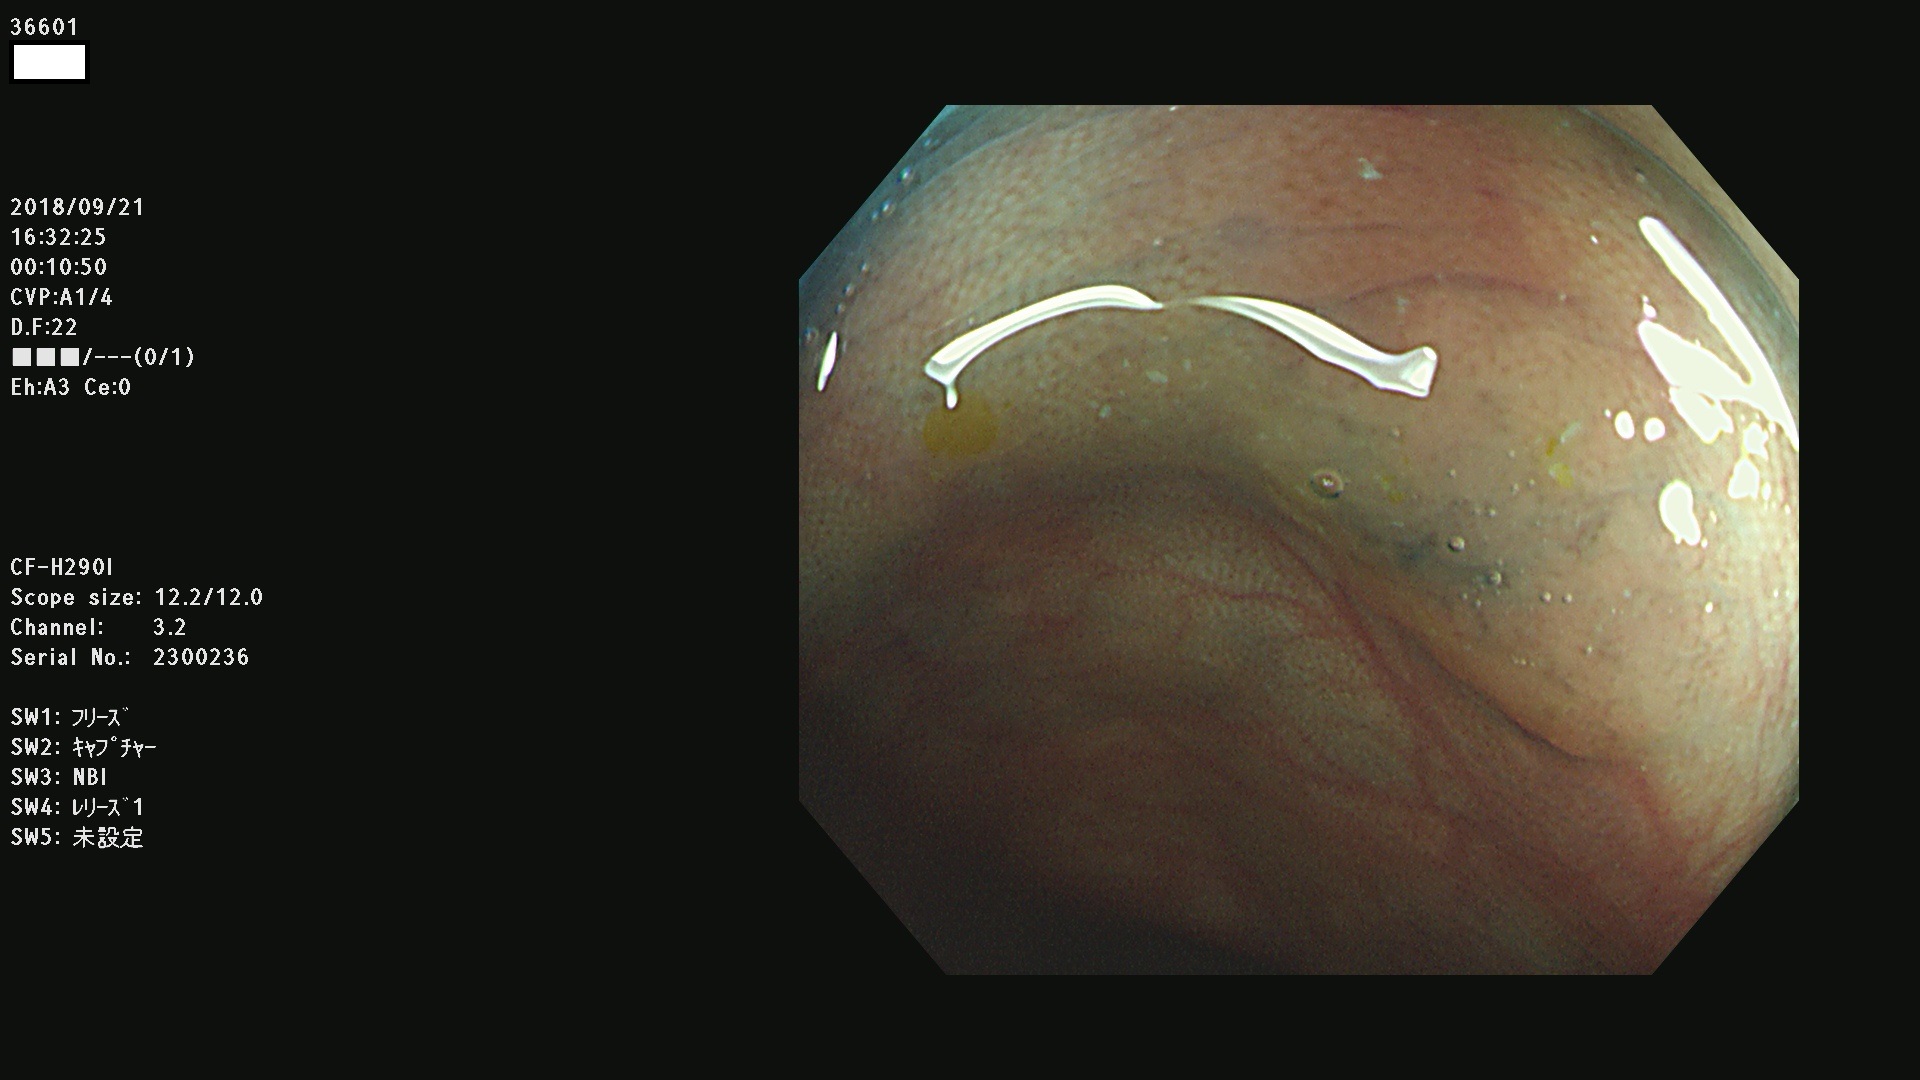

36600 36601 36603 36605 36606 36608 36609 36610 36611 36612 36613 36615 36617 36620 36621 36624 36625 36626 36627 36628 36629 36631(SSAPのみ) 36632 36633 36634 36636(SSAPのみ) 36637(SSAPのみ) 36639 36640 36642 36643 36644 36646 36647 36648 36649(SSAPのみ) 36650(SSAPのみ) 36652 36653 36654 36655(SSAPのみ) 36656 36657 36658 36659 36660 36661(SSAPのみ) 36665 36668 36669 36672 36673 36676 36677 36678 36679 36681 36682 36683 36684 36685 36687(SSAPのみ) 36691 36692 36693 36694 36695 36696 36697 36699(SSAPのみ)

発見困難で危険性の高い平坦型病変(上記100名より抽出)